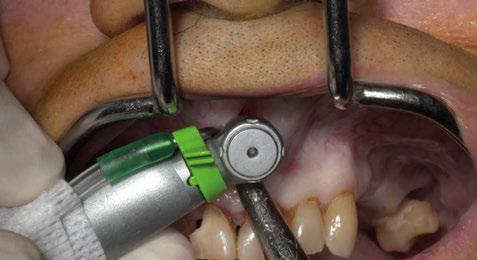

Figura 3. Intervención quirúrgica del caso clínico 1. a) situación clínica basal; b) colgajo de acceso apical vestibular y medición del defecto; c) posicionamiento ideal del injerto de tejido conectivo autólogo; d) sutura del injerto de tejido conectivo autólogo al colgajo a través del acceso apical vestibular.

Figura 4. Intervención quirúrgica del caso clínico 1. a) posición del injerto suturado a través del colgajo de acceso apical vestibular; b) utilización de aloinjerto particulado (OraGRAFT® Aloinjerto Cortical Particulado MIX 70% Mineralizado / 30% Desmineralizado) para rellenar el interior del defecto y cubrir la dehiscencia ósea; c) cobertura de la dehiscencia ósea con el aloinjerto particulado; d) customización de la lámina de cortical acorde a las características del defecto (Lámina de cortical desmineralizada Cortiflex® Salugraft Dental).

Se realiza una incisión biselada hacia coronal a espesor total en forma de parábola cóncava a apical en la mucosa labial con una hoja de bisturí no 10 alejada del fondo de vestíbulo actual. Es necesario destacar que la línea de incisión que estamos realizando se convertirá en el nuevo fondo de vestíbulo al final del procedimiento. El bisturí debe estar orientado a 45o al eje apico-coronal de los dientes. Además, la extensión mesio-distal de la incisión será acorde al número de recesiones adyacentes a tratar, debiendo extendernos idealmente un diente más a cada lado.

Una vez preparado el lecho receptor, dada la existencia de una situación combinada de recesión gingival y una dehiscencia ósea vestibular con pérdida de inserción interproximal, se opta por la utilización combinada de un injerto de tejido conectivo autólogo tuberositario, un sustituto de origen alogénico (Lámina de cortical desmineralizada Cortiflex® Salugraft Dental) que se fija mediante dos chinchetas a ambos lados, cubriendo un injerto óseo de origen alogénico particulado (OraGRAFT® Aloinjerto Cortical Particulado MIX 70% Mineralizado / 30% Desmineralizado). Primero se suturó el injerto de tejido conectivo autólogo al colgajo, después se colocaron las partículas